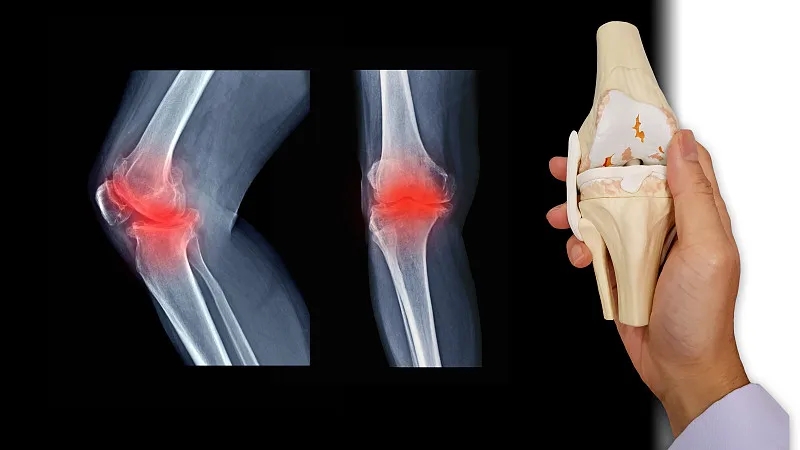

關節(jié)炎是一個通用術語,表示關節(jié)發(fā)炎。骨關節(jié)炎,俗稱磨損性關節(jié)炎,是最常見的關節(jié)炎類型。它與關節(jié)軟骨的破壞有關,并且?guī)缀蹩梢园l(fā)生在身體的任何關節(jié)中。它通常發(fā)生在臀部、膝蓋和脊柱的負重關節(jié)中。它還會影響手指、拇指、頸部和大腳趾。

軟骨是一種堅硬的橡膠狀材料,覆蓋在正常關節(jié)的骨骼末端。它的主要功能是減少關節(jié)處的摩擦,起到“減震器”的作用。正常軟骨的減震特性來自其在受壓(壓平或壓在一起)時改變形狀的能力。

骨關節(jié)炎導致關節(jié)中的軟骨變硬并失去彈性,使其更容易受到損傷。隨著時間的推移,軟骨可能會在某些區(qū)域磨損,從而大大降低其作為減震器的能力。隨著軟骨退化,肌腱和韌帶伸展,引起疼痛。如果情況惡化,骨頭可能會相互摩擦。

如何診斷骨關節(jié)炎?

您的醫(yī)生可能會使用X光檢查來幫助確認診斷并確保您沒有其他類型的關節(jié)炎。X 射線顯示發(fā)生了多少關節(jié)損傷。如果X射線結果不能明確指出關節(jié)炎或其他疾病,則可能需要進行MRI以更好地觀察關節(jié)和周圍組織。